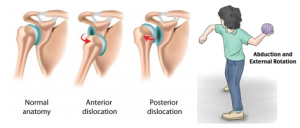

شانه یکی از متحرکترین مفصلهای بدن است و همین ویژگی، آن را آسیبپذیر میکند. وقتی فردی دچار دررفتگی مکرر شانه میشود، یعنی مفصل او بیش از یک بار از جای اصلیاش خارج شده و احتمال تکرار آن بالاست. این مشکل اگر بهدرستی درمان نشود، میتواند باعث درد مزمن، کاهش دامنه حرکتی و حتی آسیب به بافتهای مجاور شود. در کلینیک فیزیوتراپی دیاکو، ما با بهرهگیری از تجهیزات مدرن و برنامههای اختصاصی تمرینی، به بیماران کمک میکنیم تا علاوه بر درمان، از تکرار دررفتگی پیشگیری کنند.

این مشکل اغلب نتیجه آسیب اولیهای است که باعث شلشدن کپسول مفصلی یا پارگی رباطها شده است. عوامل موثر عبارتاند از: